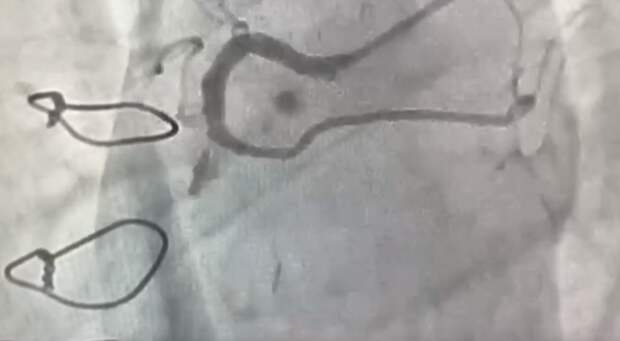

Первую операцию по коронарошунтографии провели в региональном сосудистом центре в Арзамасе. Об этом сообщил главный врач Центральной городской больницы Олег Курахтанов в соцсетях. Как отметил Олег Курахтанов, во время операции врачи проверили состояние сосудов сердца и шунтов, которые пациенту поставили осенью прошлого года после перенесенного инфаркта.

«Недавно человек стал замечать ухудшение самочувствия. Чтобы определить дальнейшую тактику лечения, в отделении рентгенохирургических методов диагностики и лечения ЦГБ Арзамаса выполнена селективная коронарошунтография», — рассказал специалист.

Коронарошунтография назначается для выявления причин стенокардии. Исследование направлено на осмотр состояния шунтов после проведённой ранее операции по аорто-коронарному шунтированию.